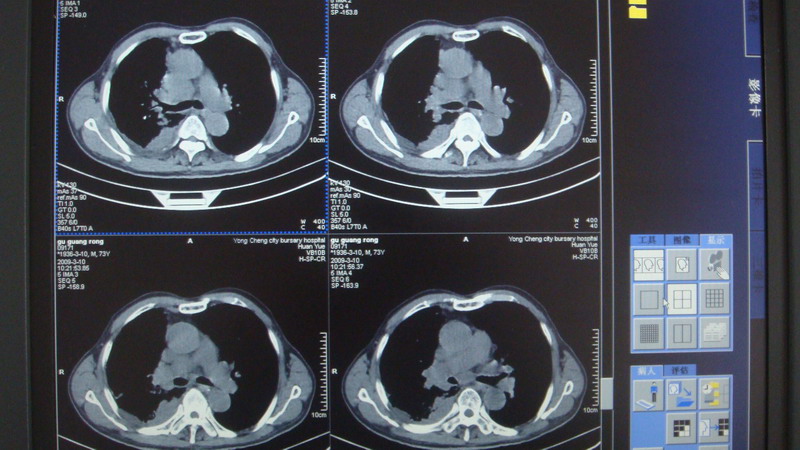

以下是引用光影相伴在2009-3-11 17:27:00的发言:[br]支持 右肺下叶周围型肺癌伴右肺门纵隔淋巴结转移;右上肺继发型肺结核(硬结\\纤维灶);右侧少量胸胸腔积液。另:不排除右侧胸膜转移可能。

以下是引用随光逐影在2009-3-11 16:57:00的发言:[br]支持 右肺下叶周围型肺癌伴右肺门纵隔淋巴结转移;右上肺继发型肺结核(硬结\\纤维灶);右侧少量胸胸腔积液。另:不排除右侧胸膜转移可能。

以下是引用草之原在2009-3-11 19:03:00的发言:[br]支持 右肺下叶周围型肺癌伴右肺门纵隔淋巴结转移;右上肺继发型肺结核(硬结\\纤维灶);右侧少量胸胸腔积液。另:不排除右侧胸膜转移可能。